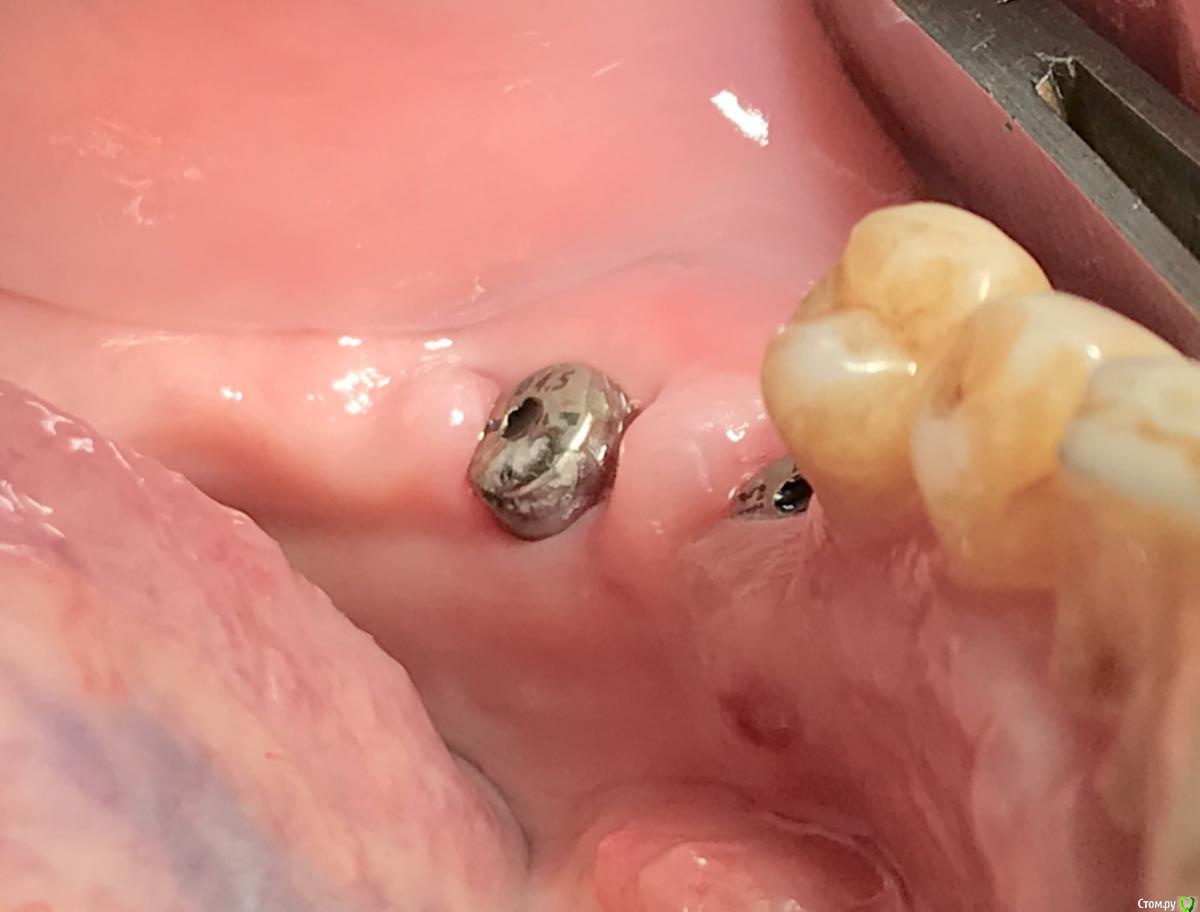

колесников Опубликовано 16 декабря, 2018 Автор Поделиться Опубликовано 16 декабря, 2018 (изменено) Поставлена задача:возместить дефект зубного ряда. Бюджет ограничен. Как видно по кт,для имплантации нет сложностей. Импланты Астра 4.0,поставлены с заглублением в оптимальной позиции. Дефицит прикреплённой слизистой вестибулярно у шеек имплантов возмещён роллом с гребня. Можно было этим ограничится. Однако при протезировании дефицит объема тканей будет очевиден. Роллы фиксированы к подвижной и тонкой слизистой,результат сомнительный,тк нет стабильности. Щечный тяж и скат гребня неминуемо приведут к рецесси слизистой у шеек имплантов. Можно было восстановить объём гребня при помощи нкр,затем лоскут с неба ( 1 год лечения). Или хотябы подсадить сст пожирнее.а потом асл (6мес),на первое время хватило бы. Но . Бюджет ограничен. Сроки тоже. Слово «костная пластика» вызывает панику. Новая задача: минимизировать вмешательства,убрать тяжи,создать объём,небо не трогаем. Проводим тоннельный графтинг. Получаем объём,поднимаем ткани и тяжи не тянут. Роллы получают покой ,стабильность и созревают в кратчайшие сроки. Графт поднадкостнично. Графт стабилен. Графт пропитался кровью,графт созревает. Результат быстрый. Дискомфорта 0. Затраты минимальные. Срок жизни такой пластики ни чем отличается от любой другой,в конечном итоге тает все. Если не стимулировать. Изменено 16 декабря, 2018 пользователем колесников 1 Ссылка на комментарий

колесников Опубликовано 19 декабря, 2018 Автор Поделиться Опубликовано 19 декабря, 2018 Чтобы ролл зафиксировать . Ссылка на комментарий